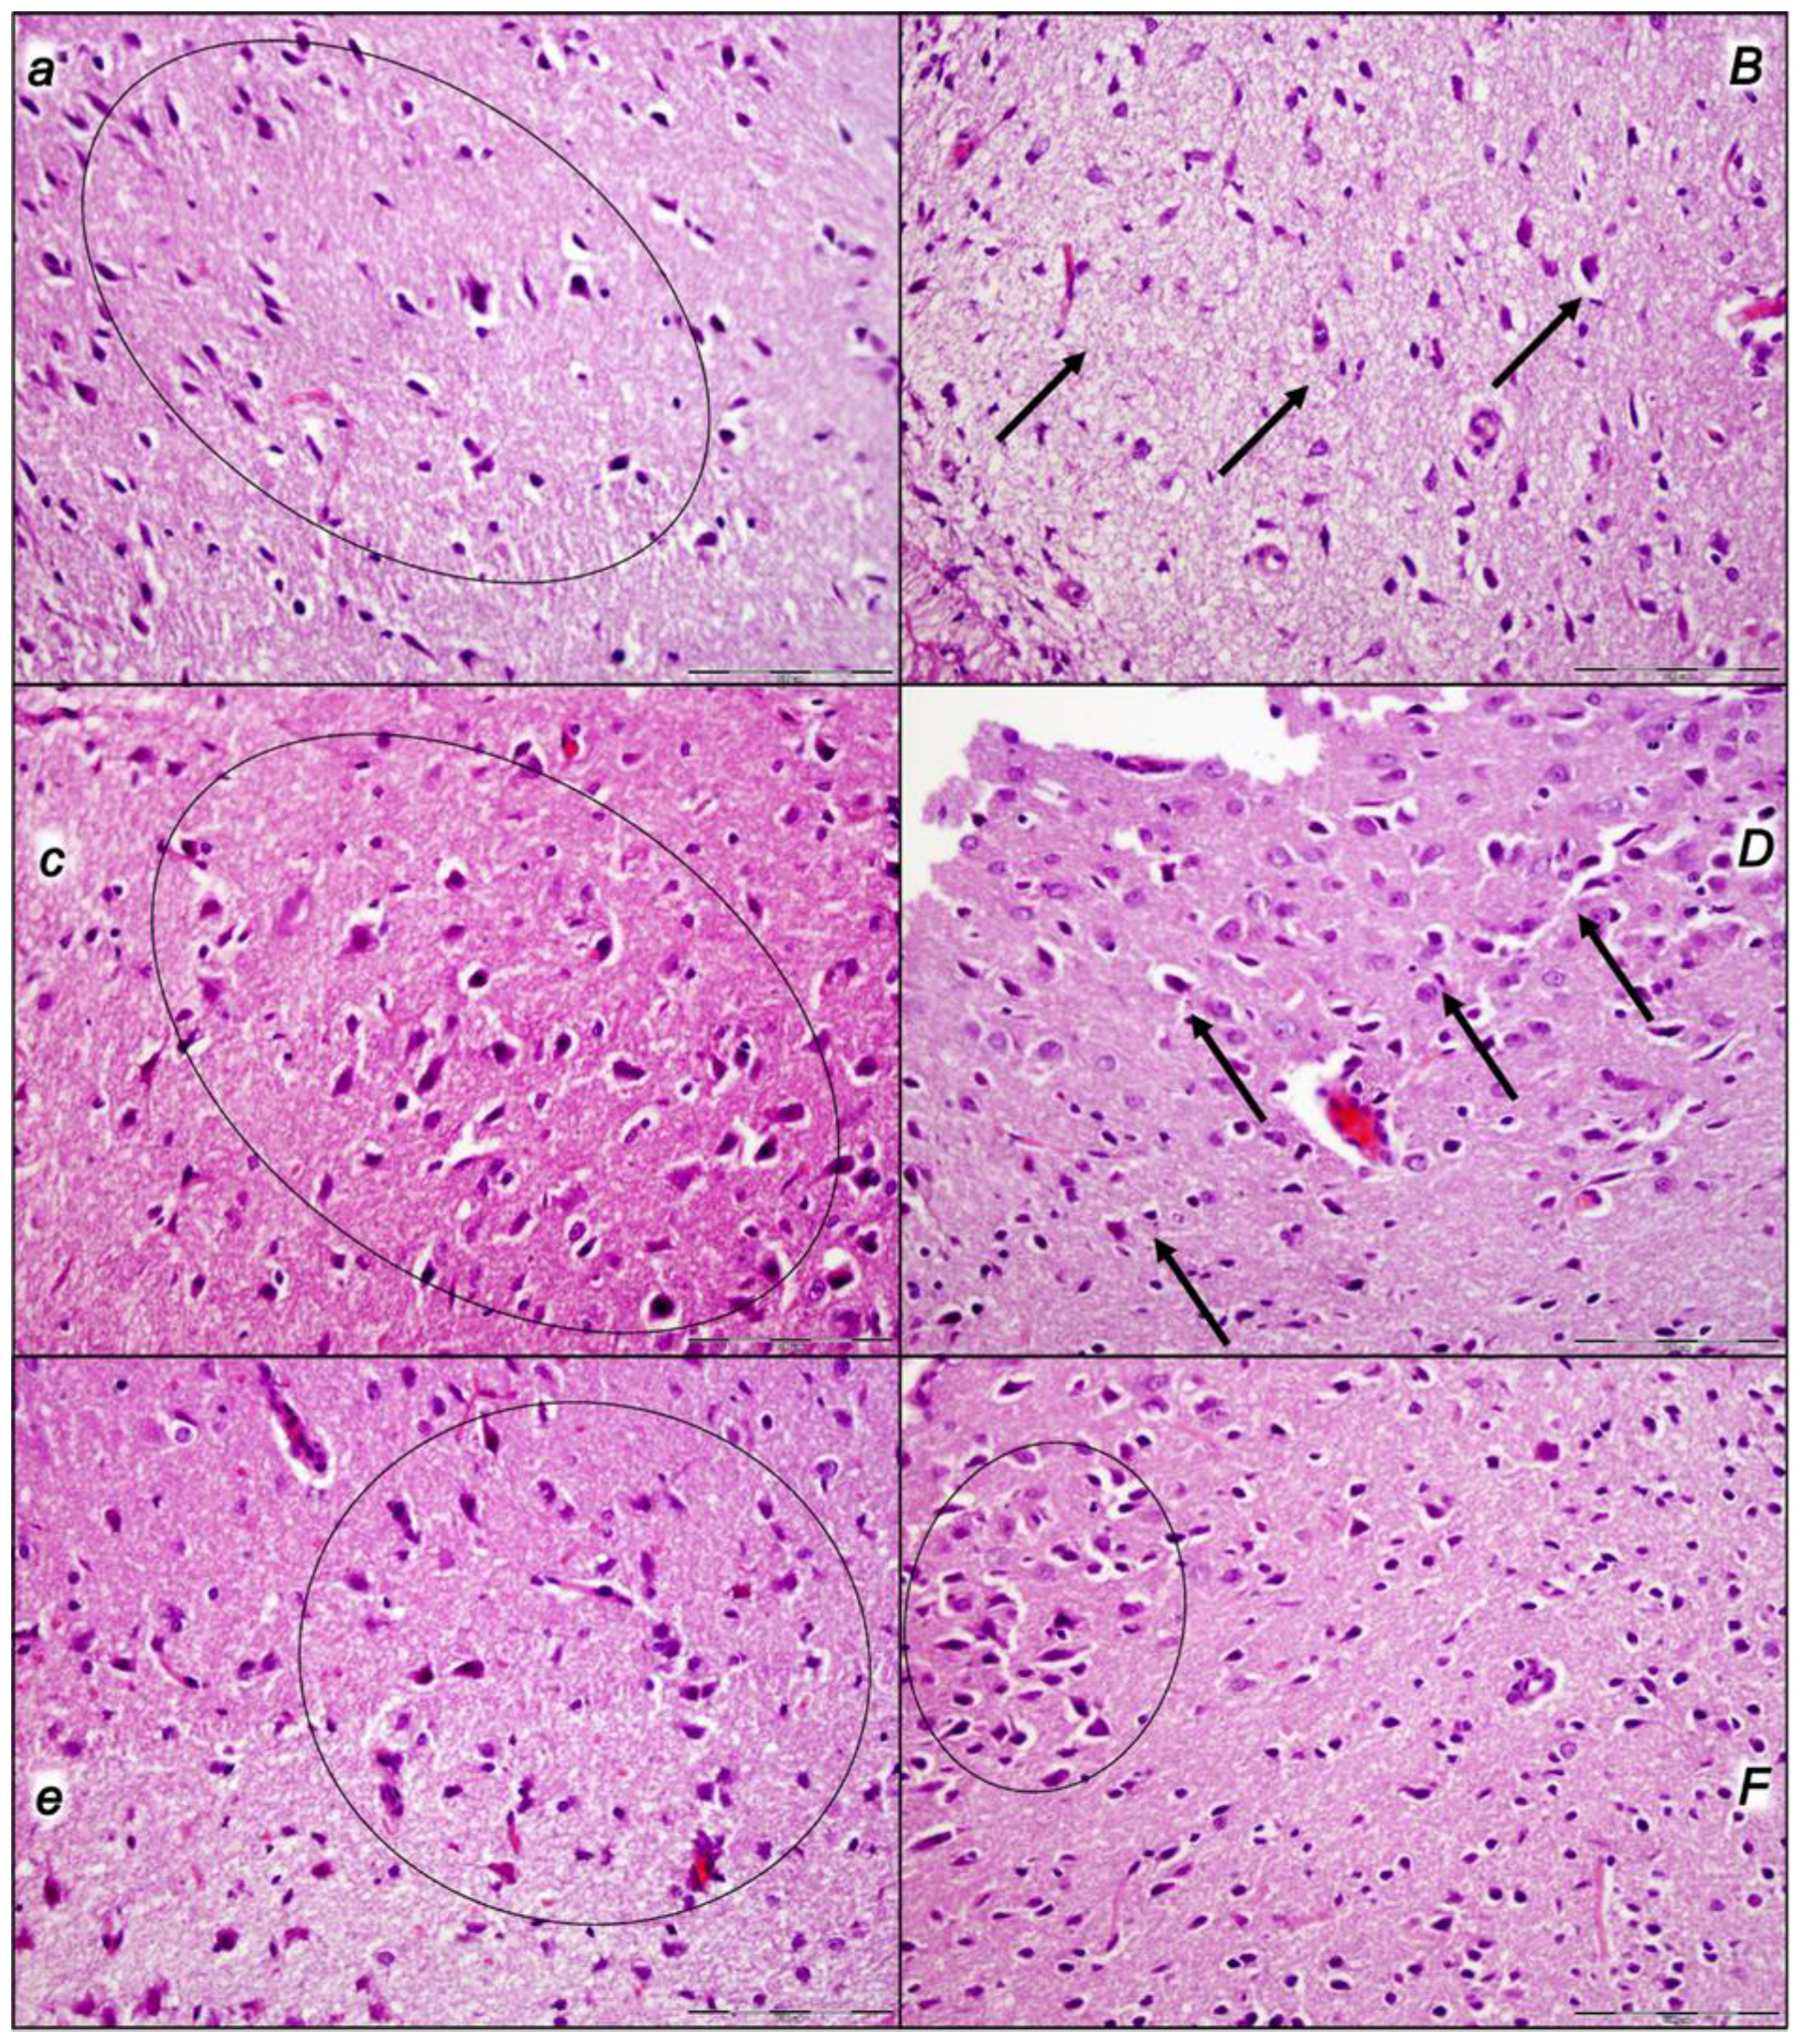

2.3.1. Brain Lesions, Cerebral and Cerebellar Cortex, Hypothalamus/Thalamus, and Hippocampus

2.3.2. Cerebrum

2.3.3. Cerebellum

2.3.4. Hippocampus

2.3.5. Hypothalamus

| Lesions, Scored Microscopically Cerebrum, Cerebellum, Hypothalamus, and Hippocampus in Rats at 60 min (i), or 30 min (ii, iii) Following Decompression after Compression with Intra-Abdominal Hypertension (25 mmHg/60min (i); 30 mmHg/30min (ii); 40 mmHg/30min (iii) | |||

| Cerebrum (scored 0–8, Min/Med/Max) # | |||

| Control | 2/3/3 | 3/3/3 | 3/3/3 |

| BPC 157 10 μg/kg | 0/1/1 * | 0/1/1 * | 0/1/1 * |

| BPC 157 10 ng/kg | 0/1/1 * | 0/1/1 * | 0/1/1 * |

| Neuronal damage in the karyopyknotic areas, %, means ± SD (10 HPF, 400×) | |||

| Control | 56 ± 5 | 64 ± 5 | 69 ± 5 |

| BPC 157 10 μg/kg | 14 ± 1 * | 18 ± 1 * | 15 ± 1 * |

| BPC 157 10 ng/kg | 16 ± 1 * | 14 ± 1 * | 17 ± 1 * |

| Hemorrhage (% of total area) | |||

| Control | 20 ± 3 | 30 ± 3 | 35 ± 3 |

| BPC 157 10 μg/kg | 2 ± 1 * | 5 ± 2 * | 5 ± 1 * |

| BPC 157 10 ng/kg | 2 ± 1 * | 6 ± 2 * | 7 ± 1 * |

| Edema (scored 0–3, Min/Med/Max) | |||

| Cerebellum (scored 0–8, Min/Med/Max) | |||

| Control | 2/2/2 | 2/2/2 | 3/3/3 |

| Control | 55 ± 5 | 61 ± 4 | 73 ± 5 |

| BPC 157 10 μg/kg | 12 ± 3 * | 16 ± 2 * | 24 ± 3 * |

| BPC 157 10 ng/kg | 15 ± 3 * | 14 ± 2 * | 22 ± 4 * |

| Hippocampus (scored 0–8, Min/Med/Max) | |||

| Control | 2/3/3 | 2/3/3 | 2/3/3 |

| Control | 24 ± 3 | 25 ± 3 | 43 ± 5 |

| BPC 157 10 μg/kg | 2 ± 1 * | 4 ± 1 * | 12 ± 2 * |

| BPC 157 10 ng/kg | 3 ± 1 * | 3 ± 1 * | 14 ± 2 * |

| Hypothalamus (scored 0–8, Min/Med/Max) | |||

| Control | 3/3/3 | 3/3/3 | 3/3/3 |

| Control | 83 ± 4 | 96 ± 4 | 94 ± 6 |

| BPC 157 10 μg/kg | 21 ± 2 * | 32 ± 2 * | 43 ± 3 * |

| BPC 157 10 ng/kg | 24 ± 2 * | 35 ± 2 * | 40 ± 3 * |

| Control | 20 ± 2 | 25 ± 5 | 25 ± 2 |

| BPC 157 10 μg/kg | 0 ± 0 * | 0 ± 0 * | 0 ± 0 * |

| BPC 157 10 ng/kg | 0 ± 0 * | 0 ± 0 * | 0 ± 0 * |